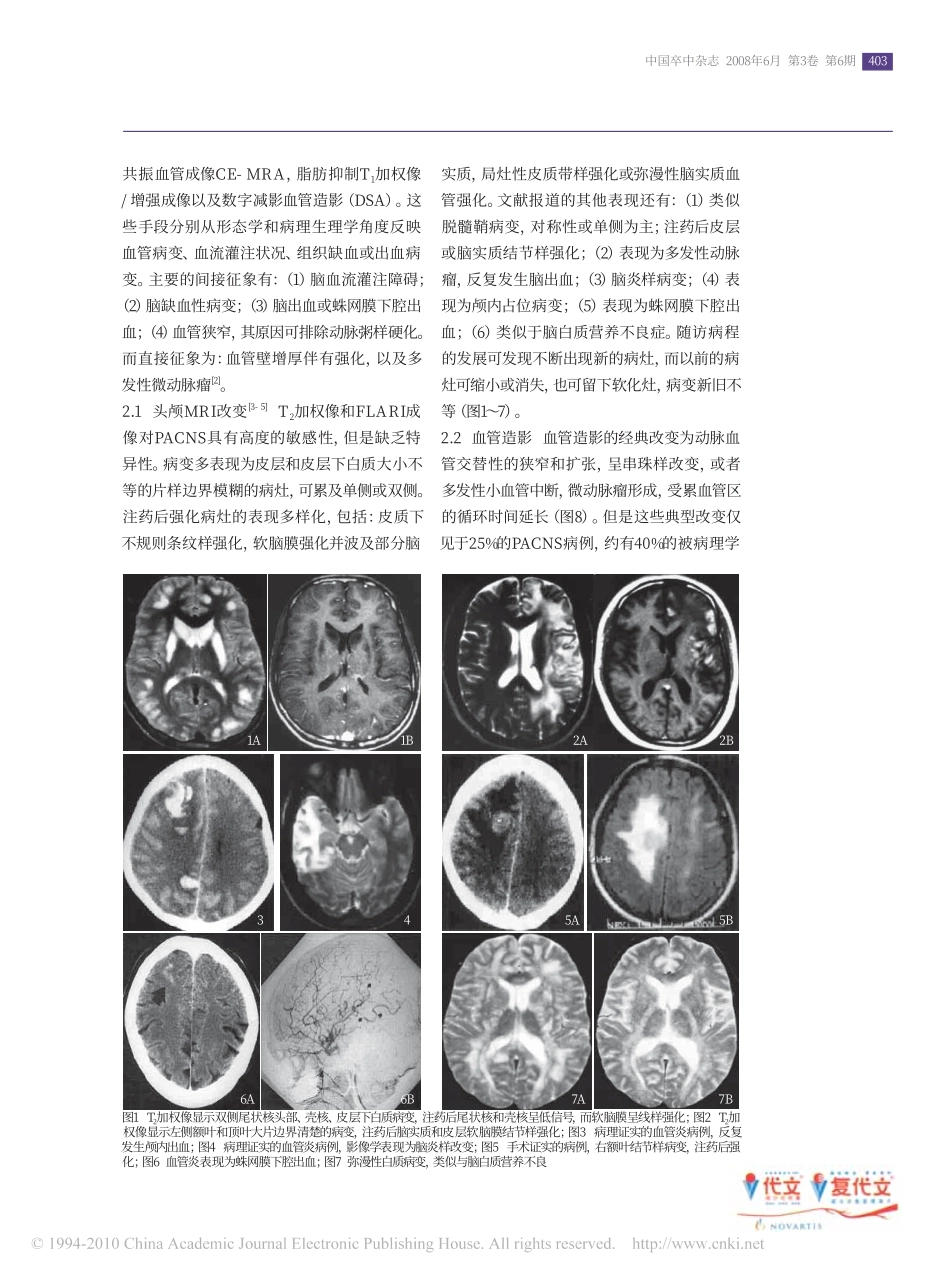

ChinJStroke,June2008,Vol3,No.6402原发性中枢神经系统血管炎的诊断策略张在强【关键词】血管炎,中枢神经系统;磁共振成像;血管造影术;病理学作者单位100050北京市首都医科大学附属北京天坛医院神经内科通信作者张在强zhangzq007@sohu.com原发性中枢神经系统血管炎(PACNS)由Cravioto和Feigin于1959年首先报道,是主要累及软脑膜、皮质和皮质下中小动脉的肉芽肿性血管炎。1983年,PACNS改称为孤立性中枢神经系统血管炎,近年来则普遍采用原发性中枢神经系统血管炎这一名称。PACNS可产生脑梗死或脑出血等严重的临床后果,早期诊断和迅速启动治疗对疾病的转归极其重要;而对疑诊为PACNS的患者,为避免长期使用免疫抑制治疗,准确地鉴别诊断显得更为关键。PACNS发病率较低,目前尚无准确和敏感的诊断试验。由于PACNS临床表现多样化、缺乏特异性等特点给临床诊断带来了严重的挑战。近年来,许多研究者依据PACNS的形态学和病理生理学特征对诊断方法进行了探讨,逐渐形成了PACNS的诊断路径。1PACNS的临床表现和临床分类任何年龄均可发病,以中青年多见,无明显的性别差异,临床表现从脑血管症候群到脑膜脑病综合征,变化多样:可急性起病,也可隐袭性发病,多为慢性病程,缓解与复发交替。主要表现为头痛、意识障碍、认知能力下降、偏瘫、精神症状、性发作、失语、短暂性脑缺血发作、脑出血、视力障碍或失明、脊髓病变等,可有全身性症状如发热、皮疹、关节疼痛,少数可有体重下降。根据临床和病理特点可将PACNS分为四种亚型[1]:(1)中枢神经系统肉芽肿性血管炎(GACNS):为PACNS最为严重的类型,约占20%。主要累及小至中等大小的血管,一般隐袭性起病,出现头痛、性发作,局灶性或弥漫性神经功能缺损。血管造影多正常,皮层和软脑膜活检是诊断本病的金标准,但有大约25%病例出现假阴性结果。本病主要与肉芽肿性感染,神经结节病和血管内淋巴瘤等鉴别;(2)中枢神经系统良性血管病(BACNS):1993年命名,临床结局优于GACNS,但常常导致卒中,进而死亡。典型临床表现为:突发性剧烈头痛,紧随其后发生卒中(见于40%的病例),脑脊液检查正常,脑活检提示血管正常,血管造影显示:多血管床交替性的扩张和狭窄。但在症状发生后3~4个月,血管造影的异常呈可逆性变化。现在认为BACNS是血管痉挛,类似于Call-Fleming综合征、产后血管病、偏头痛血管痉挛和药物诱导的“血管炎”等病,所有这些疾病现在均命名为可逆性脑血管收缩综合征;(3)非典型PACNS:大多数PACNS属于这种类型,病理改变为淋巴细胞性血管炎,无肉芽肿形成;(4)孤立占位病变型:约占5%,表现为头痛、抽搐和局灶性神经功能缺损。影像学表现为占位病变,有占位效应,水肿,注药后强化。常易误诊为肿瘤或脓肿。2PACNS的影像学改变常用于PACNS诊断的影像学技术包括常规头颅磁共振成像(MRI)、液体衰减反转恢复成像(FLAIR)、弥散加权成像(DWI)、灌注加权成像(PWI),梯度回波成像,时间飞跃法磁共振血管成像(TOF-MRA),对比增加磁403中国卒中杂志2008年6月第3卷第6期共振血管成像CE-MRA,脂肪抑制T1加权像/增强成像以及数字减影血管造影(DSA)。这些手段分别从形态学和病理生理学角度反映血管病变、血流灌注状况、组织缺血或出血病变。主要的间接征象有:(1)脑血流灌注障碍;(2)脑缺血性病变;(3)脑出血或蛛网膜下腔出血;(4)血管狭窄,其原因可排除动脉粥样硬化。而直接征象为:血管壁增厚伴有强化,以及多发性微动脉瘤[2]。2.1头颅MRI改变[3-5]T2加权像和FLARI成像对PACNS具有高度的敏感性,但是缺乏特异性。病变多表现为皮层和皮层下白质大小不等的片样边界模糊的病灶,可累及单侧或双侧。注药后强化病灶的表现多样化,包括:皮质下不规则条纹样强化,软脑膜强化并波及部分脑图1T2加权像显示双侧尾状核头部、壳核、皮层下白质病变,注药后尾状核和壳核呈低信号,而软脑膜呈线样强化;图2T2加权像显示左侧额叶和顶叶大片边界清楚的病变,注药后脑实质和皮层软脑膜结节样强化;图3病理证实的血管炎病例,反复发生颅内出血;图4病理证实的血管炎病例,影像学表现为脑炎样改变;图5手术证实的病例,右...